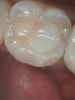

Figure 1 shows a pretreatment photograph of a tooth No. 20. In Figure 2, the circled area of the x-ray indicates the interproximal area where the clinician was uncertain if caries was present. Though x-rays are useful, transillumination is more sensitive and optimal for detecting caries in the early stages.12 With new devices, clinicians can acquire more information before working on the tooth. As shown in Figure 3, caries was confirmed using the transillumination system (CariVu), though it did not show up on an x-ray. The clinician was able to show the image to the patient. The open-tooth camera image then revealed the extent of the caries in the exact position that was displayed in the transillumination image (Figure 4). This is a significant advantage in minimizing preparations and saving valuable tooth structure.

Fig 1. Pretreatment photograph, tooth No. 20.

Figure 1